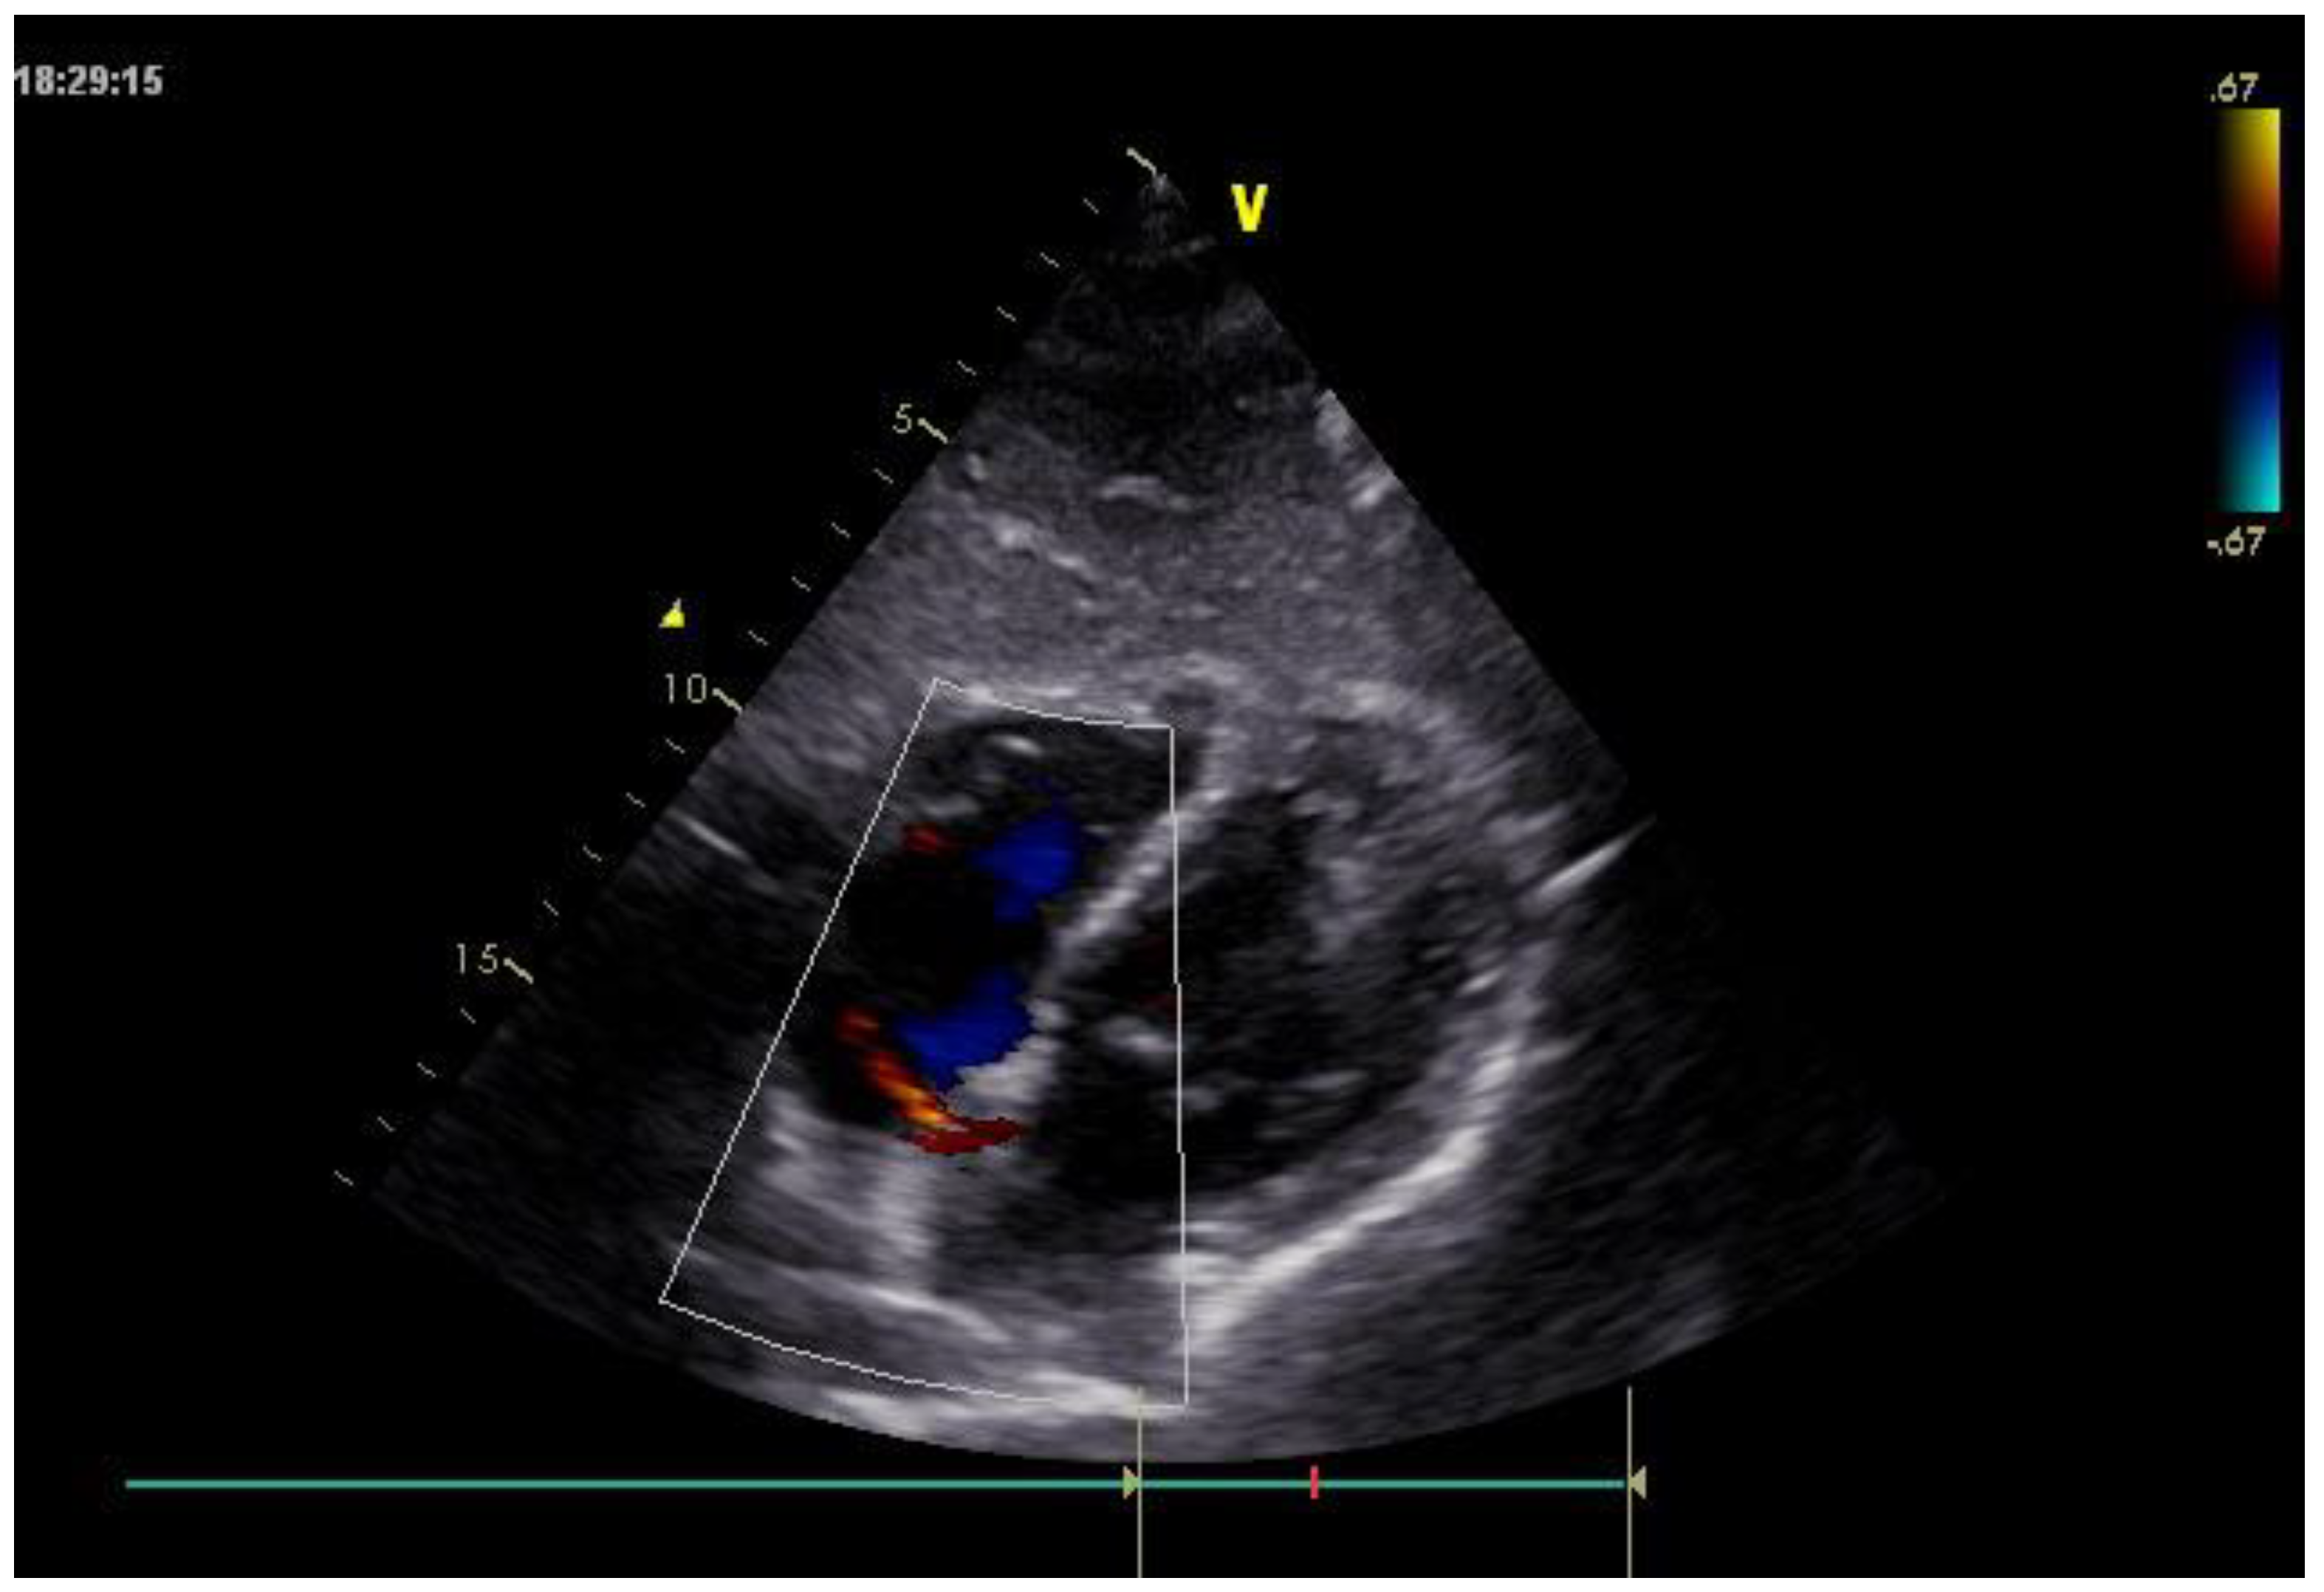

Furthermore, transthoracic echocardiography performed on admission confirmed the absence of the Amplatzer device at the interatrial septum and demonstrated a residual left-to-right shunt across the atrial septum (Figure 2).

Figure 2. Transthoracic echocardiography showing absence of the Amplatzer device at the interatrial septum and evidence of a residual left-to-right shunt across the atrial septum.